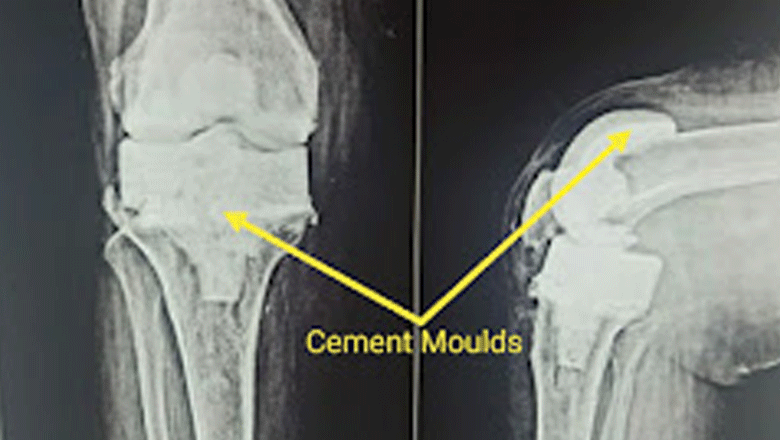

Partial Knee Replacement (PKR)

We carry out Partial Knee Replacement (PKR) for patients with early-stage knee damage, aiming to preserve as much healthy bone and tissue as possible while improving movement and reducing pain.

Best For:

- Early arthritis of knee

- Unicompartmental arthritis